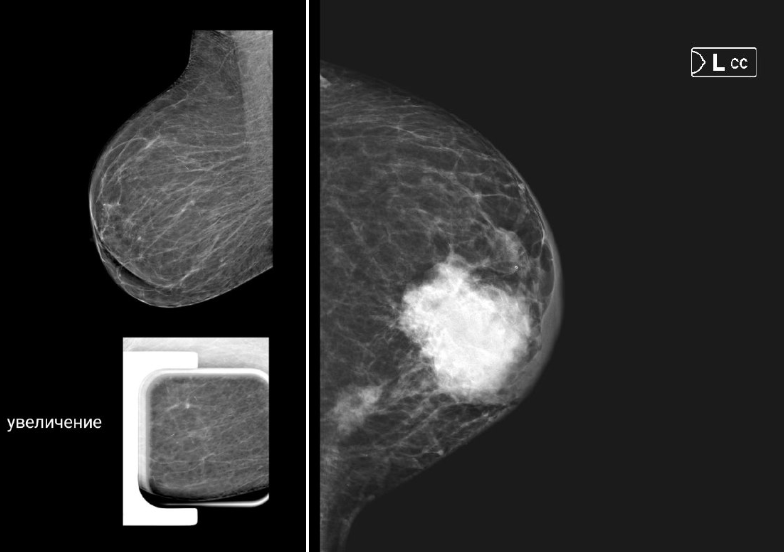

2 снимка маммографии. На обоих рак молочной железы, но какая разная ситуация. Сегодня мы говорим о стадии - распространенность рака в молочной железе и во всем организме. От нее зависит многое: от ощущений пациентки до плана лечения и шансов на будущее. Давайте сравним эти две точки — начало и распространенную форму болезни. Клиническая картина: что чувствует женщина На 1ом снимке (1 стадия -опухоль 5 мм) болезнь почти «немая». Чаще всего это просто небольшое уплотнение в груди, которое не болит и никак не мешает жить. Его можно нащупать случайно или увидеть на маммограмме. Ни слабости, ни боли, ни изменений в самочувствии нет. Женщина может отлично себя чувствовать и даже не подозревать о проблеме. На 2 снимке опухоль распространена в молочной железе и регионарных л/узлах (в данном случае - это 3 стадия). Организм кричит о беде. Опухоль видна визуально, отмечается уплотнение, изменение формы молочной железы, пальпируются л/узлы. Опухоль может прорастать в кожу, вызывая её изменен

На 1ом снимке (1 стадия -опухоль 5 мм) болезнь почти «немая». Чаще всего это просто небольшое уплотнение в груди, которое не болит и никак не мешает жить. Его можно нащупать случайно или увидеть на маммограмме. Ни слабости, ни боли, ни изменений в самочувствии нет. Женщина может отлично себя чувствовать и даже не подозревать о проблеме.

На 2 снимке опухоль распространена в молочной железе и регионарных л/узлах (в данном случае - это 3 стадия). Организм кричит о беде. Опухоль видна визуально, отмечается уплотнение, изменение формы молочной железы, пальпируются л/узлы. Опухоль может прорастать в кожу, вызывая её изменение (симптом «лимонной корочки», покраснение, язва), или в мышцу. Но главный признак — поражение регионарных лимфоузлов в подмышечной впадине, около ключицы или грудины. Могут появиться боли, дискомфорт, отёк руки. Организм уже тратит силы на борьбу, поэтому возможны усталость и недомогание.